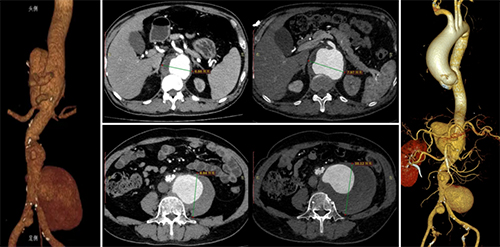

经4个月的抗感染治疗后,感染指标恢复正常,血培养阴性,复查瘤体增大约1cm(如下图示),仍有腰腹部疼痛不适症状,决定行台上改制开窗-分支支架治疗。

抗布病药物治疗前后4个月复查CT可见:瘤体增大约1cm

手术在全麻下实施,根据术前CT测量数据转化为平面图,根据图纸改制支架开窗并缝制短分支后,经双侧股动脉、左腋动脉入路植入体内过程顺利,术毕造影可见瘤体隔绝满意,分支动脉血流通畅(如下图示)。术后腰腹痛症状缓解,术后第4天顺利出院。随访3年期间瘤体逐渐缩小,无明显内漏,无感染复发。

手术过程图示:根据术前CT数据转化成平面图,台上改制支架并植入体内隔绝瘤体并重建脏动脉分支血流;术后复查可见瘤体逐渐缩小,支架形态良好,分支血流通畅